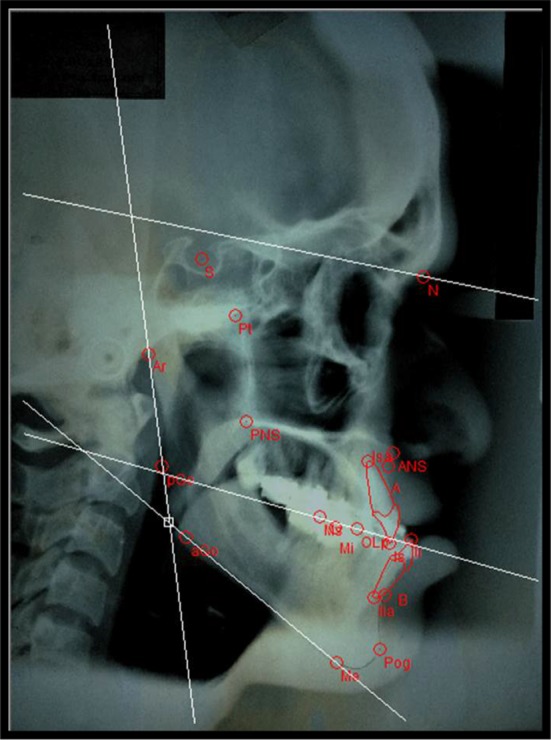

Fig. 1.

Presurgical COGS hard tissue